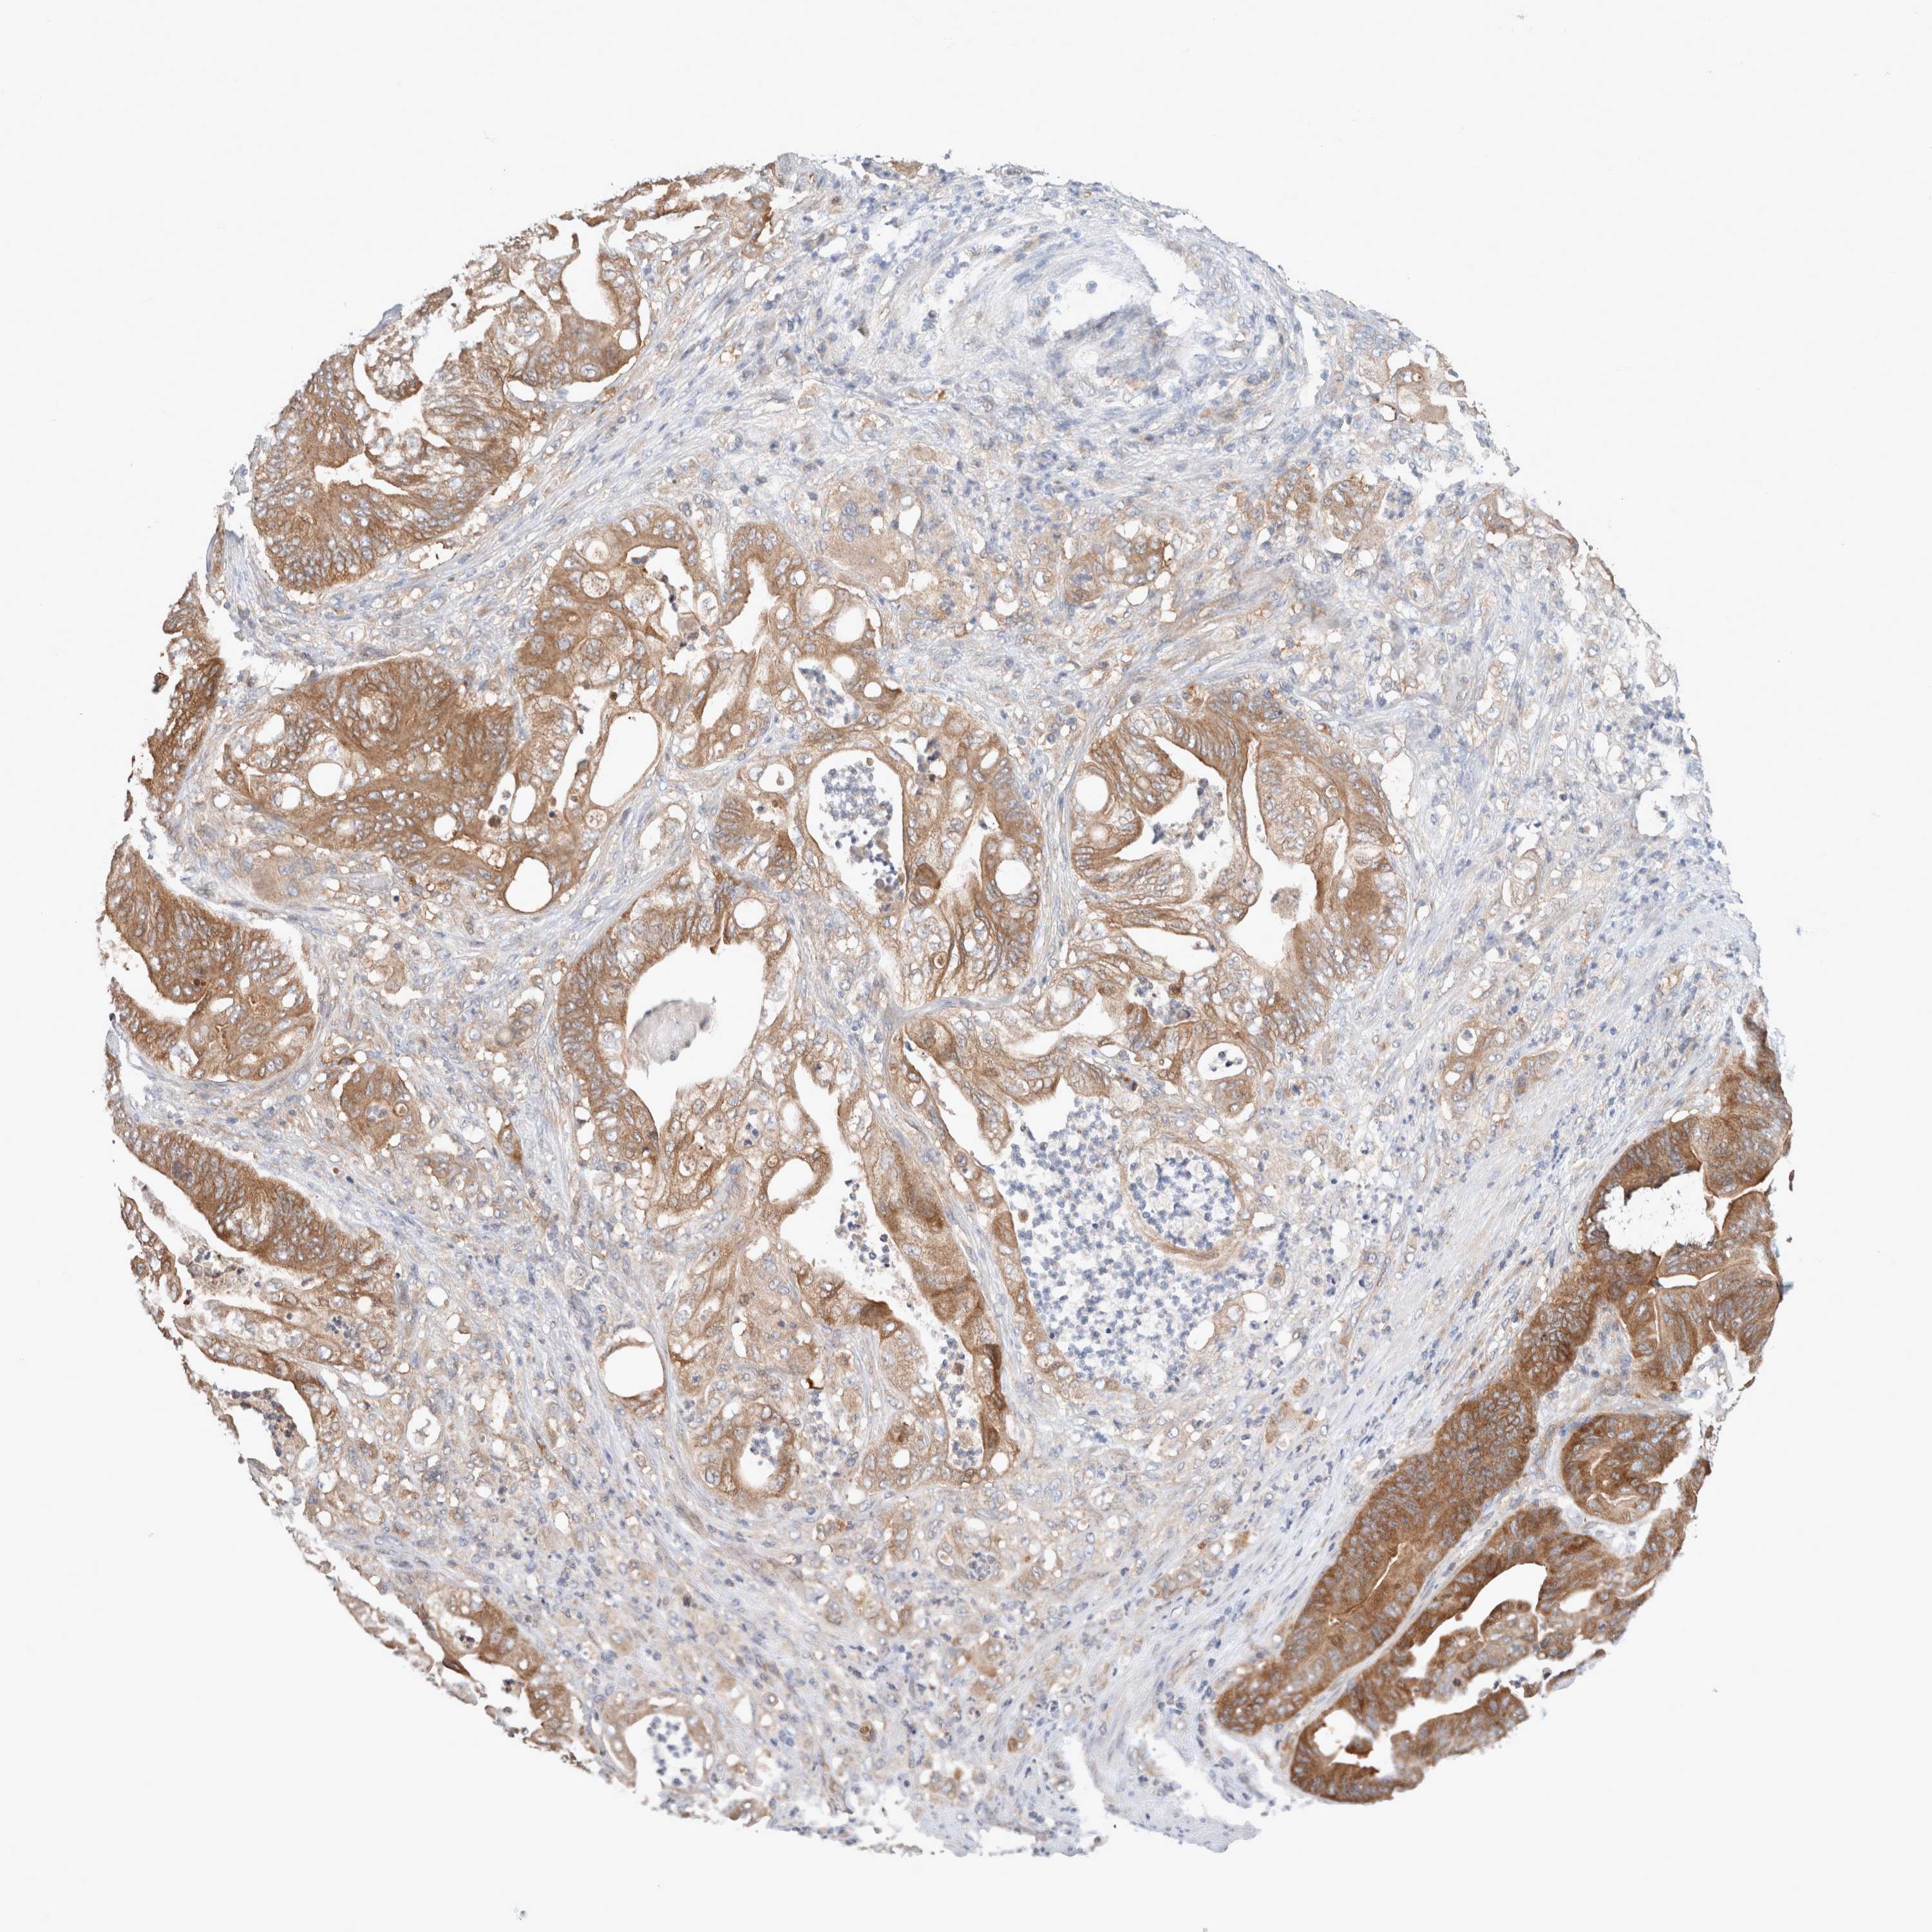

STOMACH CANCER - Protein expressioni

A mouse-over function shows sample information and annotation data. Click on an image to view it in a full screen mode. Samples can be filtered based on level of antibody staining by selecting one or several of the following categories: high, medium, low and not detected. The assay and annotation is described here.

Note that samples used for immunohistochemistry by the Human Protein Atlas do not correspond to samples in the TCGA dataset.

Antibody stainingi

Antibody staining in the annotated cell types in the current human tissue is reported as not detected, low, medium, or high, based on conventional immunohistochemistry profiling in selected tissues. This score is based on the combination of the staining intensity and fraction of stained cells.

Each image is clickable and will lead to virtual microscopy that enables deeper exploration of all samples and also displays staining intensity scores, fraction scores and subcellular localization as well as patient and tissue information for each sample.

HPA030419

HPA030420

HPA030422

CAB025196

CAB080286

CAB080287

Staining

High

Medium

Low

Not detected

Intensity

Strong

Moderate

Weak

Negative

Quantity

>75%

75%-25%

<25%

None

Location

Nuclear

Cytoplasmic/membranous

Cytoplasmic/membranous,nuclear

Adenocarcinoma, NOS

Adenocarcinoma, High grade